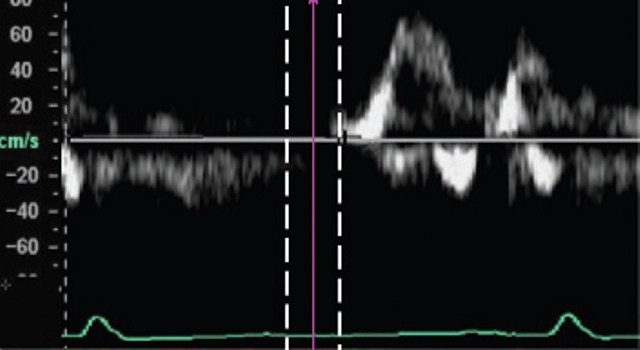

Який режим УЗД-дослідженя грунтується

на ефекті зміни частоти та довжини хвилі, що спостерігається при русі

джерела хвиль щодо їх приймача.

Знайти відповідність між графічною візуалізацією кривої та її назвою.